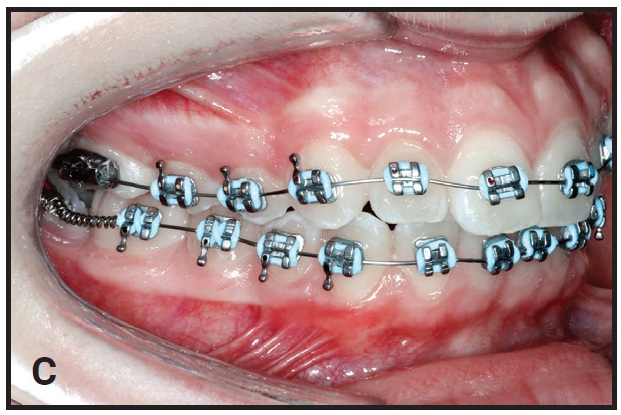

A mandibular second-premolar twin bracket is bonded to the mesiobuccal cusp of the first molar. The bracket’s curved base adapts nicely to the molar surface (B). Using a twin bracket instead of a standard first-molar tube makes it easier to thread the archwire through the second-molar tube and compress the open-coil spring (C). Moreover, the spring can be placed over the initial nickel titanium wire at the bonding appointment.